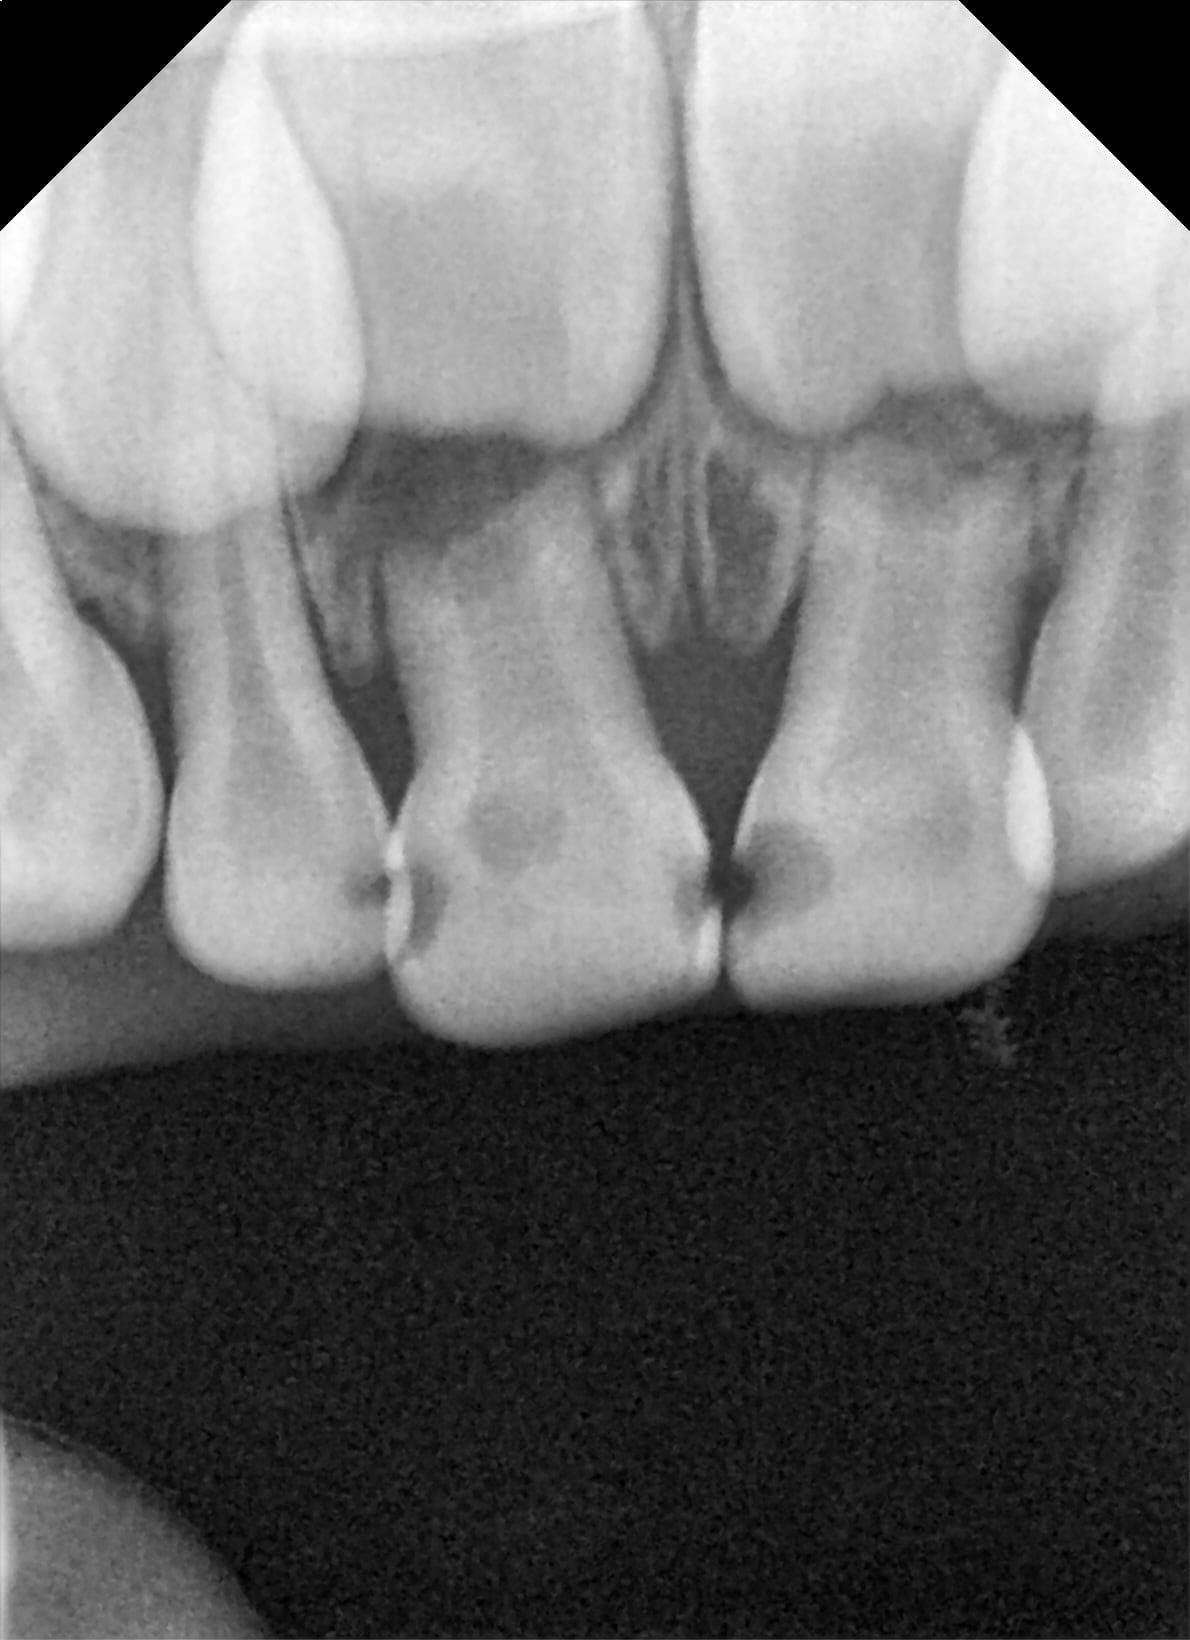

Capture_d_écran_2019-09-05_08.53.43_xrhdot.png